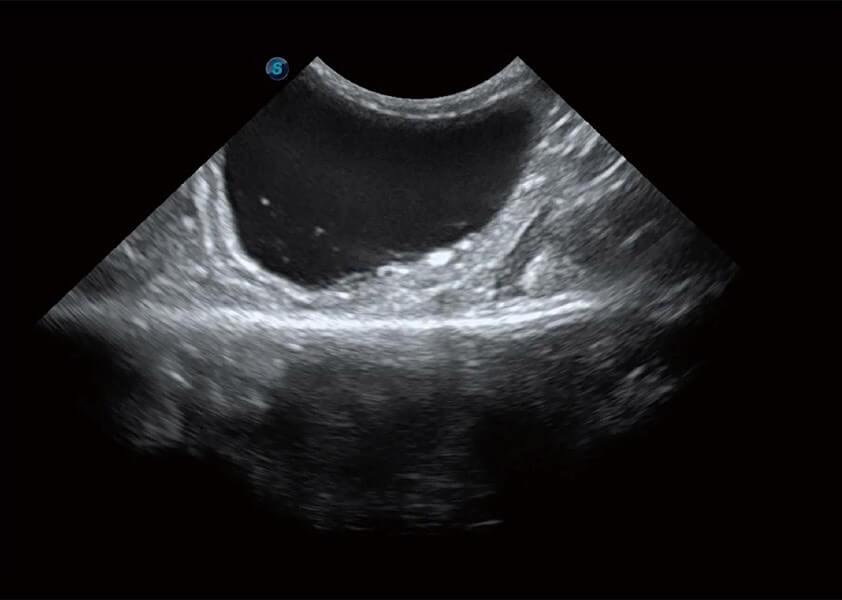

ProPet 60 作为一款高端台式动物超声设备,为动物医生的日常诊断提供了一系列贴合动物临床需求、解决临床实际问题的高级成像功能。凭借全系列高清探头,满足医生对腹部、心脏、生殖、浅表、肌骨等成像的所有需求,切实帮助您提升检查效率,提高诊断信心。

动物是人类最亲密的朋友和最值得信赖的伙伴。玖鼎集团也一直致力于探索动物专用的超声影像解决方案。 全新推出的ProPet系列,是玖鼎集团在动物超声影像智能化、专业化、精准化的一次跨越式革新。动物不能用言语来表述自己的不适,通过超声影像,ProPet系列搭建了动物医生与不同物种沟通的“桥梁”,为动物医生注入了“治愈之力”。